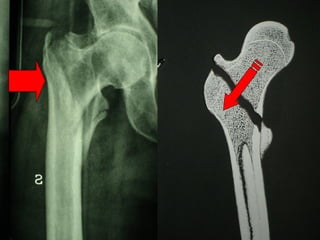

La placca a compressione percutanea (PC.C.P.) di Gotfried è un mezzo di sintesi studiato per assicurare un “impattamento controllato” delle fratture pertrocanteriche grazie alle due viti telescopiche prossimali che garantiscono una ottima stabilità rotazionale

Tradizionalmente si ritiene importante per la stabilità delle fratture pertrocanteriche l’integrità della parte mediale della metafisi prossimale del femore

In realtà la zona più importante per la ricostruzione di questo tipo di fratture è il muro laterale contro il quale si impatta il frammento metaepifisario mediale

Se il muro laterale è rotto o viene lesionato durante la sintesi , come spesso accade in fase di applicazione della vite cefalica dei chiodi endomidollari o della vite-placca, andremo incontro al collasso della frattura e ad un conseguente lungo periodo di impotenza funzionale

Con la placca di Gotfried non si è mai riscontrato un danno iatrogeno del muro laterale e nessun collasso della frattura.Ciò è dovuto al fatto che i fori per l’applicazione delle due viti prossimali sono di piccolo diametro (9 mm) rispetto ai 16-32 mm necessari per introdurre la vite cefalica di un chiodo endomidollare o di una vite-placca a compressione.